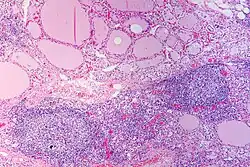

Coupe histologique d'une thyroïde atteinte par la maladie en coloration hématoxyline-éosine, montrant l'infiltration lymphoïde avec notamment la présence de follicules.

Sur le plan physiopathologique, les anticorps dirigés contre la thyroperoxydase et/ou la thyroglobuline causent une destruction progressive des follicules thyroïdiens de la glande thyroïde.

Macroscopiquement, le goitre est symétrique, non adhérent aux éléments péri-thyroïdiens et présente une surface capsulaire discrètement bosselée[1].

En microscopie les lésions consistent en une association de fibrose interstitielle, d'infiltration lymphoïde et de destruction épithéliale[1],[2]. Le degré de fibrose est très variable[1]. L'infiltration lymphoïde présente une organisation en follicules avec des lymphocytes B au centre et des lymphocytes T dans le cortex[2]. Les cellules épithéliales thyroïdiennes sont également modifiées, apparaissant élargies et acidophiles (cellules de Hürthle)[2].